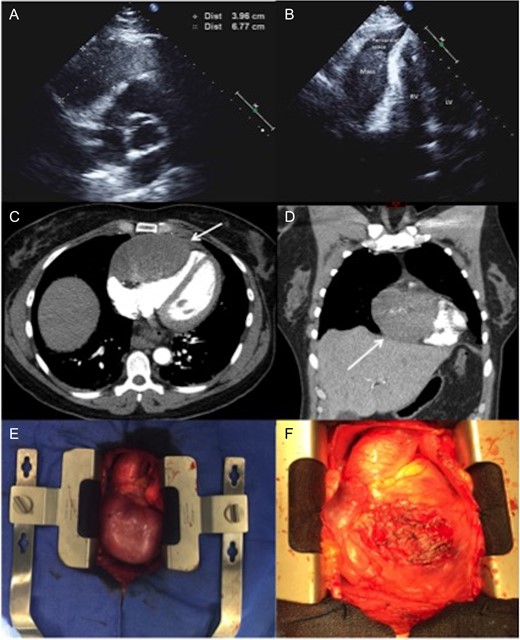

A healthy 49-year-old female with history of hysterectomy for uterine leiomyoma was referred to our hospital with tachycardia and acute onset of chest pain. On admission, the patient reported having intermittent shortness of breath and back pain for several years that significantly progressed one-week prior the presentation. The chest pain had both pleuritic and positional components, no heart murmurs or other significant clinical findings were identified. The hematological and biochemical investigations were normal. Subsequent transthoracic echocardiogram showed a round hypoechoic mass within the pericardial space. The tumor was in direct contact with the right ventricle, with no signs of local invasion. There was mild compressive effect with preserved ejection fraction of 50–55% (Figure 1). Computer tomographic (CT) angiography of the chest confirmed an 80 × 60 mm, well-circumcised solid mass of unknown origin. There was no evidence of other primary tumors or acute pulmonary thrombo-embolic disease. CT guided biopsy for tissue characterization revealed a benign spindle cell tumor. The immunohistochemical stains showed tumor cells that are strongly positive for Estrogen and Progesterone receptors (ER and PR) in addition to Smooth Muscle Actin (SMA), Desmin and Caldesmin.

(A and B) Two-dimensional echocardiography. An apical two-chamber view reveals a well-circumscribed, oval hypoechoic mass with maximal diameter of 67 mm. (C and D) Axial and coronal CTA imaging of the tumor showing the direct contact and compression effect to the right ventricle. (E)—Intraoperative pictures demonstrating a large tumor adherent to the right ventricle. (F) The heart after removing of the tumor: almost entire anterior surface of the right ventricle has been involved. LV, left ventricle; RV, right ventricle; CTA, computer tomographic angiography.

The lack of local invasion, the general mass appearance and the pathologic evaluation of the CT guided biopsy suggested a benign nature of the tumor. Additional imaging such as cardiac MRI, PET-CT and TEE (transesophageal echocardiogram) were considered. After multidisciplinary discussion we decided to proceed directly with the operative management of the tumor, taking into account the compression effect and the pronounced symptoms of the patient.

During a subsequent transsternal exploration, a broad-based mass was found to be originating from the visceral pericardium, tightly attached to the underlying right ventricle with no infiltration of the parietal pericardium (Figure 1). The 80 × 65 mm tumor was excised from the right ventricle without the need to place the patient on cardiopulmonary bypass (Figure 2).